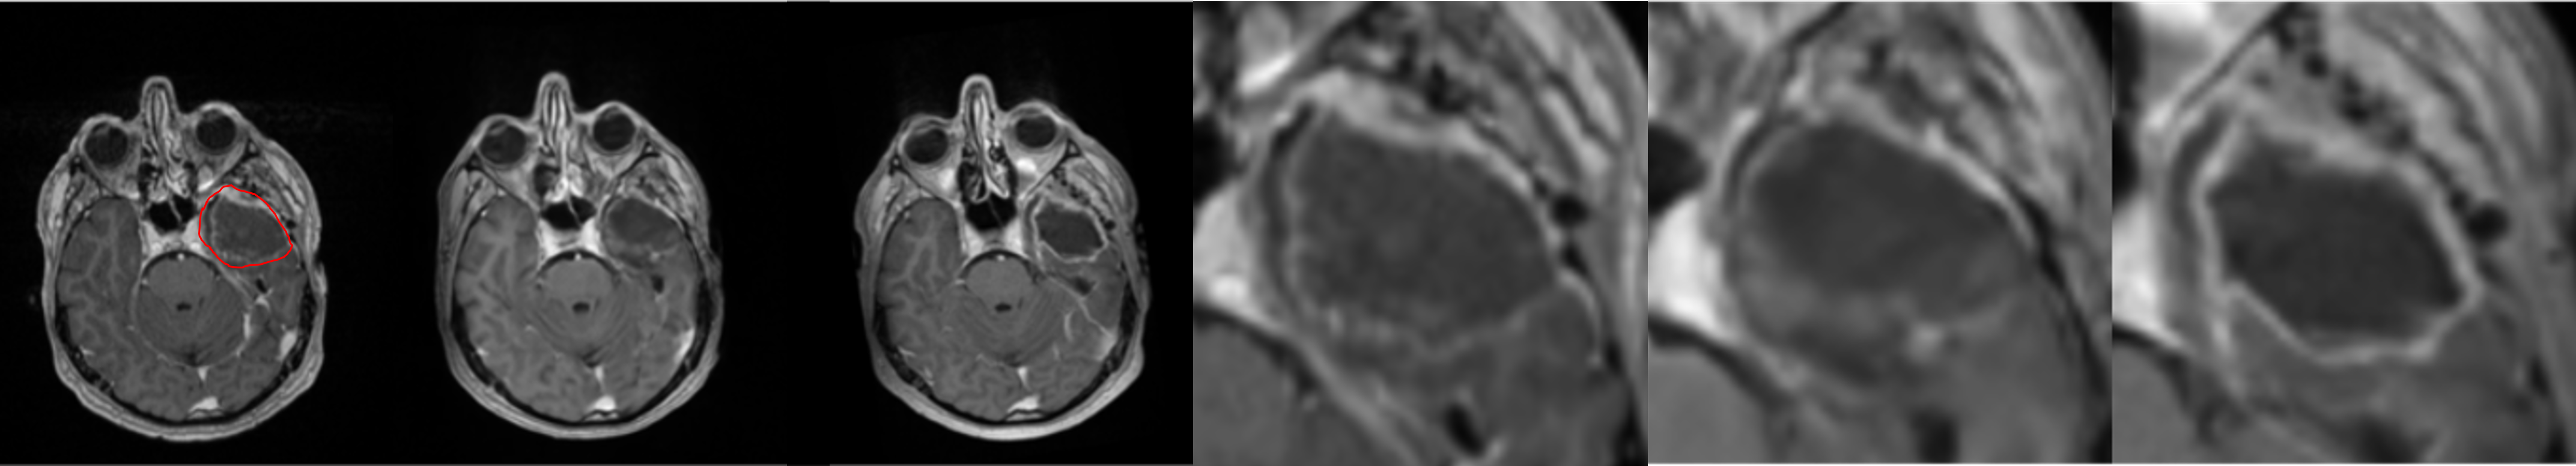

To further illustrate the model’s performance we retained only the pred 2-class model, as it reflects a realistic use case. We present several generated examples in Fig. 4. The first row corresponds to the highest local SSIM score (0.71), depicts a patient who underwent total resection, where tumor progression is minimal. We observe that the model fails to predict the hyper-intensity in the periphery of the tumor (T1-enhancement) in comparison to the ground truth. In contrast, the last row corresponds to the lowest SSIM score (0.02), making it an edge case. We observe that the model generally failed to predict T1-enhancement localized to the tumor area; however, it succeeded in predicting the necrotic area.